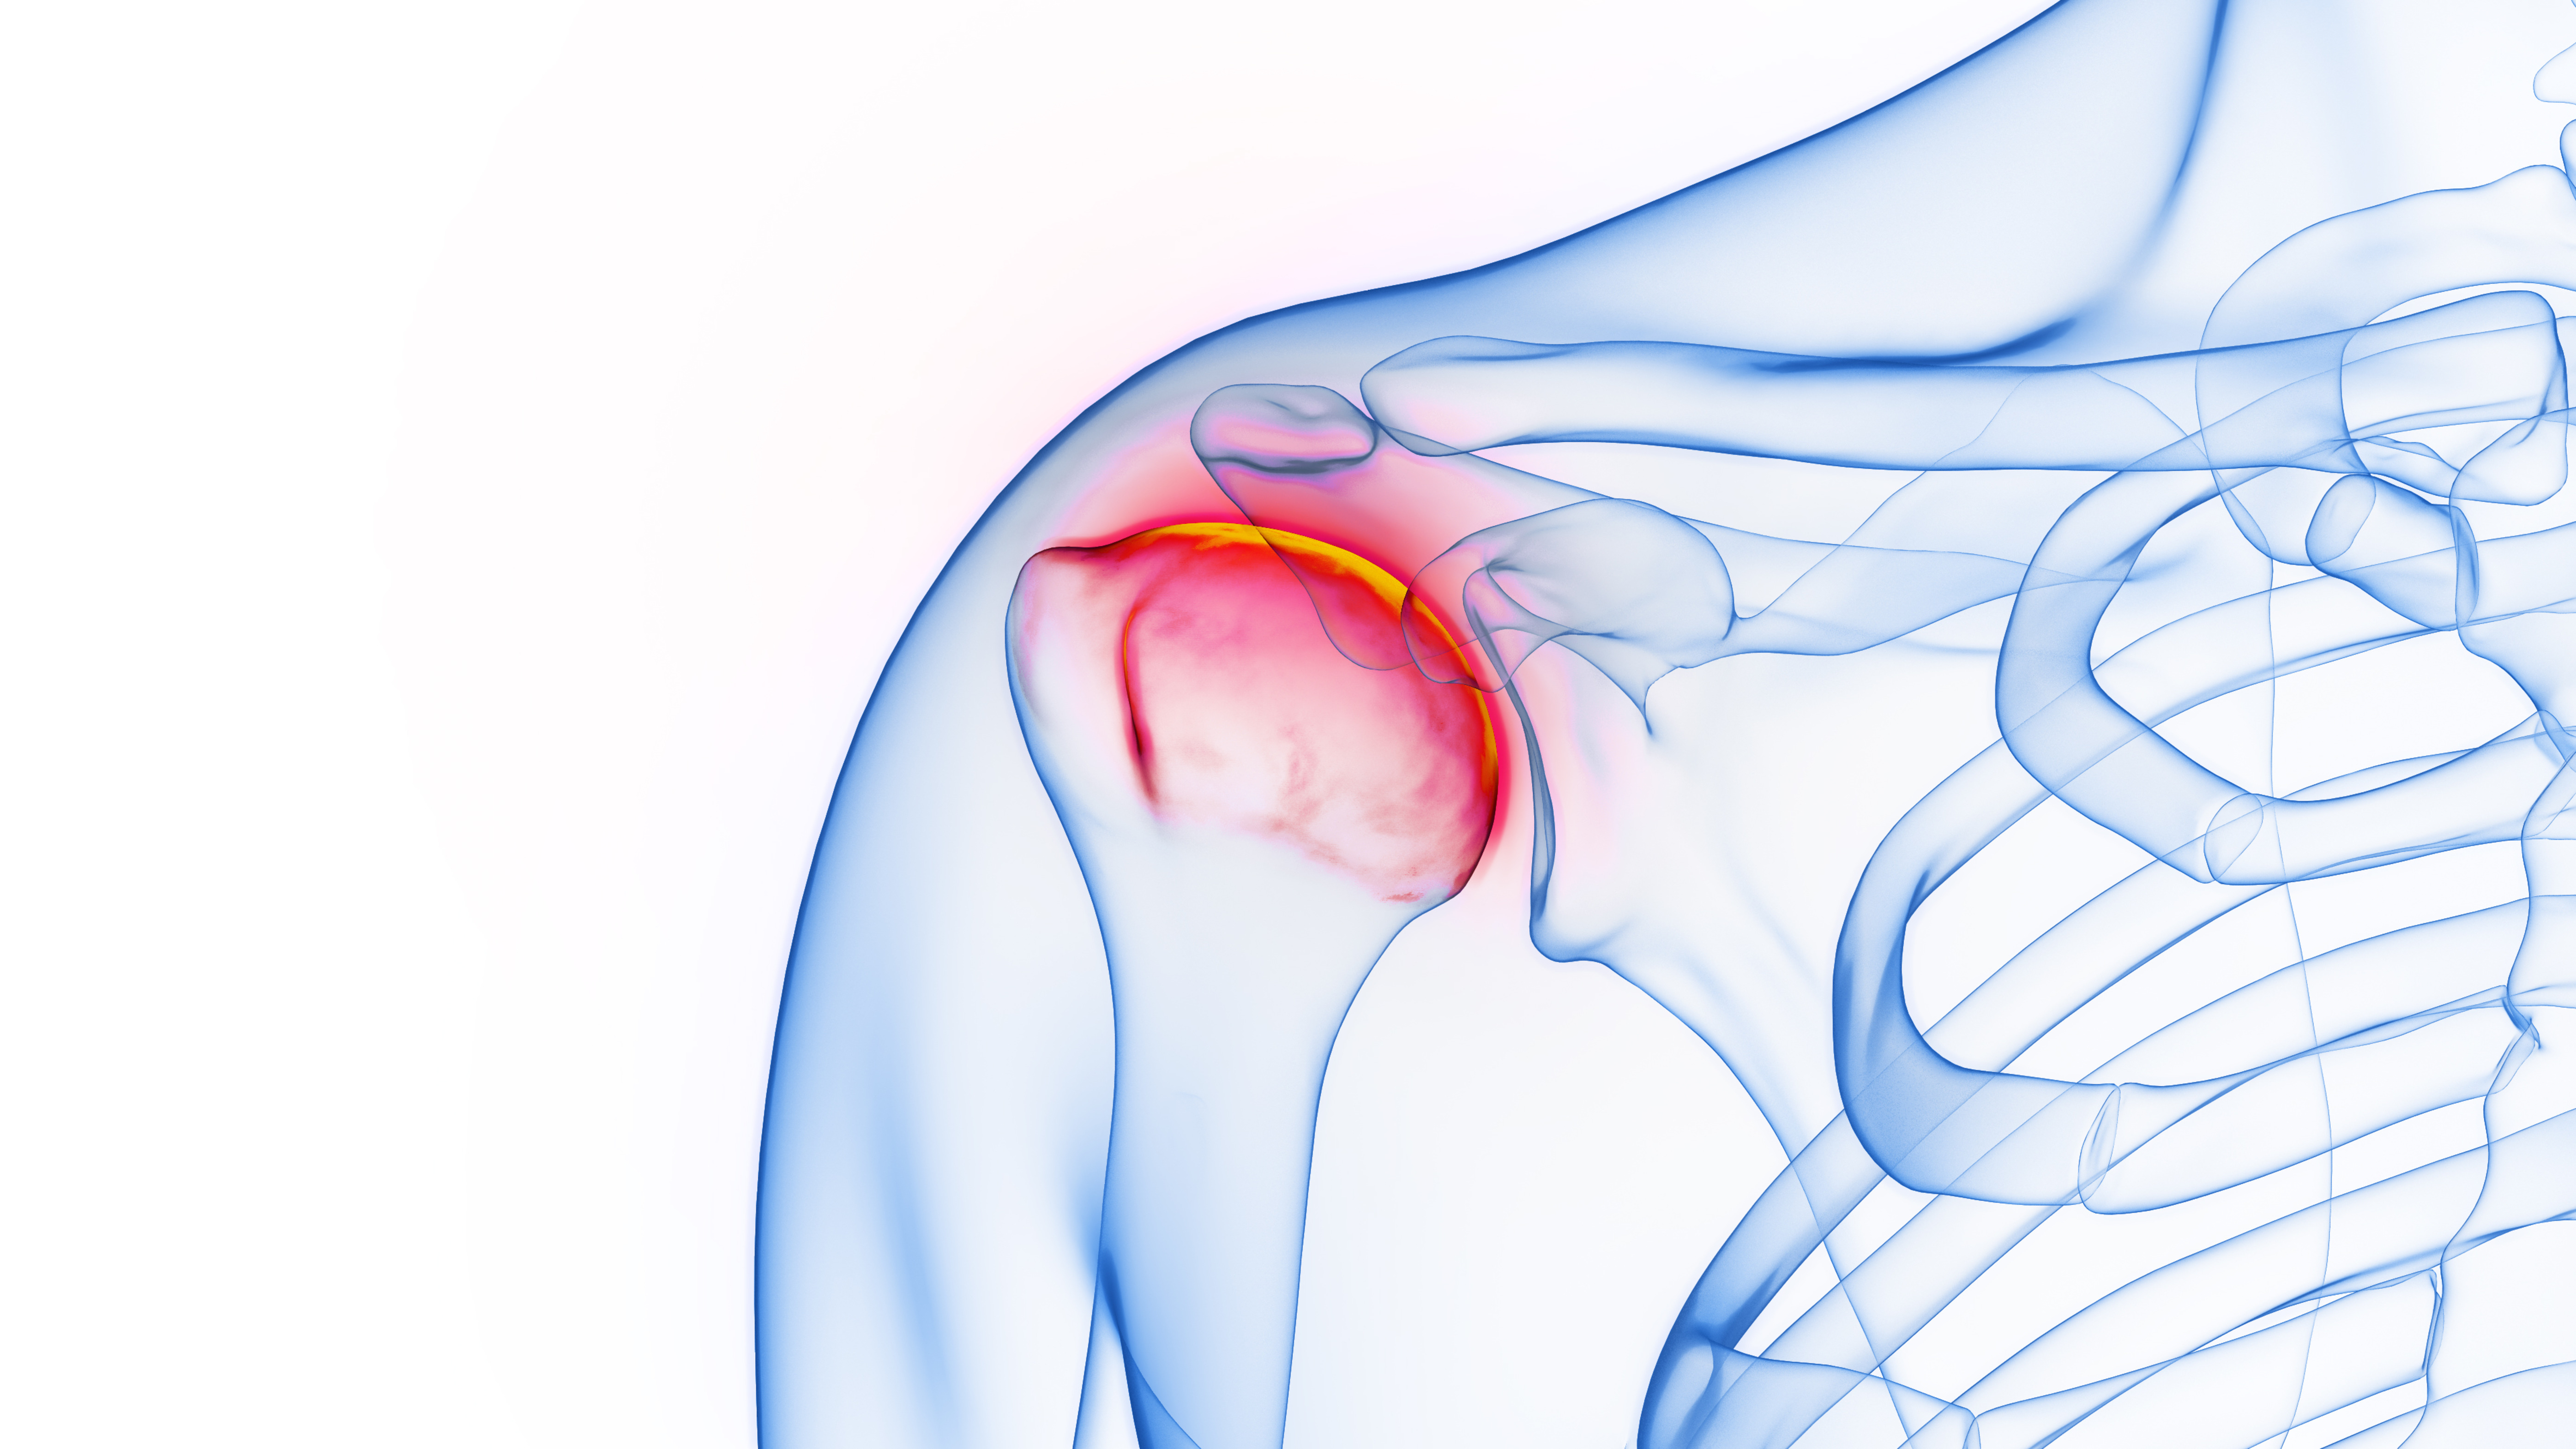

치료

약물 및 주사치료를 통해 관절막의 염증을 완화시키며 도수치료 및 체외충격파 치료와 병행하여 굳은 관절을 풀어줍니다. 또한 수압팽창술로 자극을 주는 석회부분을

떨어뜨립니다.

관절내시경을 통해 두꺼워진 관절막을 제거합니다.